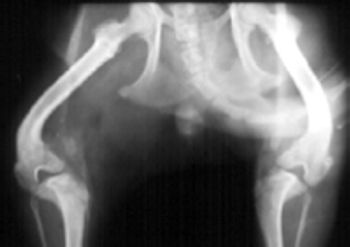

CHD has been called inherited, a developmental disease, and most accurately in the author's opinion, a "moderately heritable disease". CHD is a multifactorial disease with part of its cause being from genetic influences (estimated at 25%-80%) and part from environmental influences.

The best treatment for degenerative joint disease is prevention, by removing the inciting cause before DJD is established if at all possible (TPO, JPS, cruciate stabilization, patella stabilization, etc.) Irreversible changes of DJD (visible in the form or periarticular osteophytes) are present by 28 days after the cause is present.